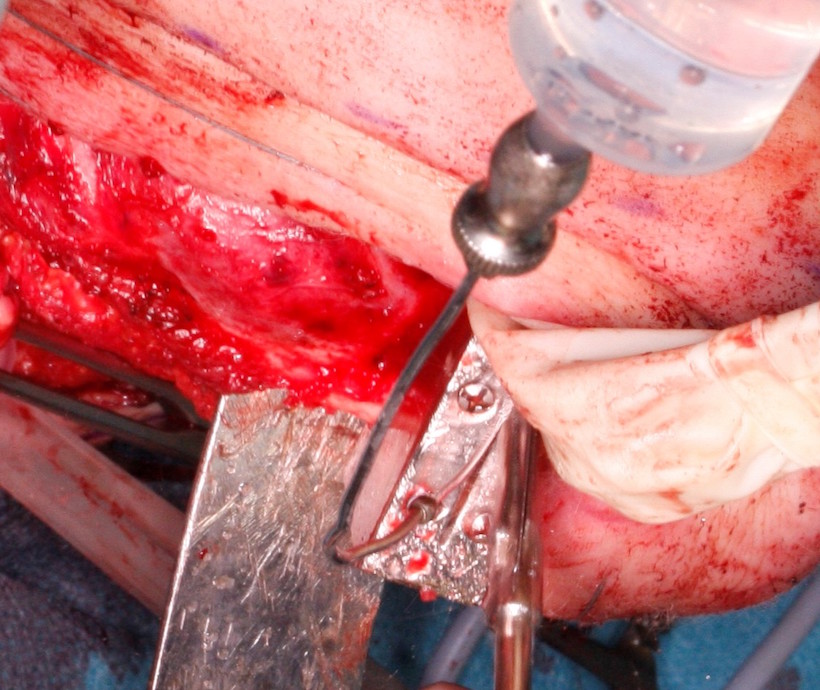

W dniu 19.05.2021 wykonano zabieg w znieczuleniu ogólnym. Z cięcia przedusznego Redona po stronie prawej oraz Shaha w środkowym fałdzie szyi pod kontrolą neuronawigacji odsłonięto sktruktury anatomiczne szyi. Wypreparowano i odcięto prawą tętnicę i żyłę twarzową do mikrozespoleń. Następnie odsłonięto trzon, kąt, gałąź i wyrostek dziobiasty żuchwy po stronie prawej (Fig. 8.). Okrojono wewnątrzustnie błonę śluzową w zakresie planowanej resekcji i po stunelizowaniu tkanek żuchwę zresekowano na pełną grubość od zęba 42 do gałęzi żuchwy u podstawy wyrostka dziobiastego zachowując cienką mufkę mięśniową nad rozdęciami żuchwy spowodowanymi przez guz wewnątrzkostny. Resekcję wykonano przy użyciu wcześniej przygotowanych indywidualnych szablonów chirurgicznych. (Fig.9., 10.). Ranę wewnątrzustnie zeszyto warstwowo. Założono wyciąg międzyszczękowy w zwarciu prawidłowym pacjentki na śrubach typu Fast-fix.

Fig. 8. Wypreparowany z dostępu zewnątrzustnego guz żuchwy po stronie prawej (strzałka)

Fig. 9. Resekcja w zakresie trzonu żuchwy z użyciem indywidualnego szablony chirurgicznego